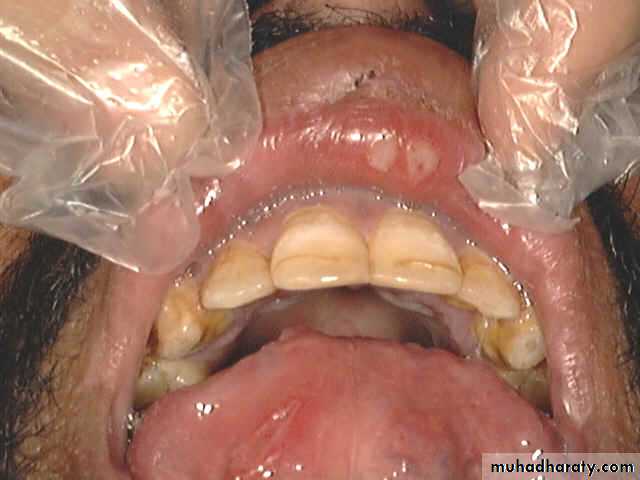

Acute follicular tonsillitis

Peritonsillar Abscess( Quinsy)

Is a collection of pus between the fibrous capsule of the tonsil and the superior constrictor.Usually unilateral, Adult males.

Complication of acute tonsillitis.

Clinical Picture

1. The patient looks ill, feverish with rigor .2. Acute sore throat & referred otalgia, Odynophagia). This makes the saliva dribbles from the month.

3. Trismus: irritation of the pterygoid muscles .

4. Thick and muffled voice often called “hot potato

voice”.

Examination

1. The tonsil is congested and pushed medially with the soft palate bulging downward and forward.

The uvula may be pressed against the opposite tonsil.

2. Red and enlarged anterior tonsillar pillar.

3. Tender and enlarged cervical lymph nodes